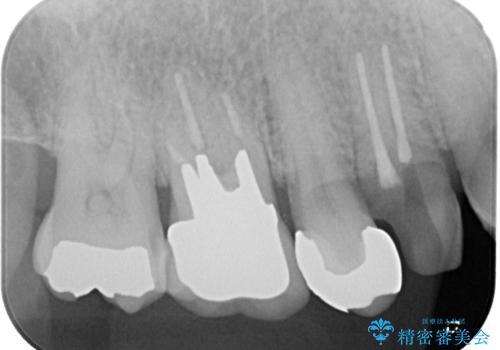

- 抜歯が必要なのでは?と近医で言われ、歯の保存を希望して来院された患者様です。

既に別の部位にインプラント治療を受けており、そのときの治療期間と苦労を鑑みて、何とか歯を残したいとのことで来院されました。

該当歯の状態としては何とか保存可能でしたが、予後不良のため、将来的にインプラント治療が必要となる可能性の高い状態でした。

当院での根管治療および歯周外科治療を併用した保存療法、並びに1DAYインプラントによる短期間インプラント治療の双方をご説明し、即日でインプラント治療を選択されました。

仮歯を用意した上で、抜歯即時埋入・即時荷重インプラントによる補綴治療を行うこととしました。